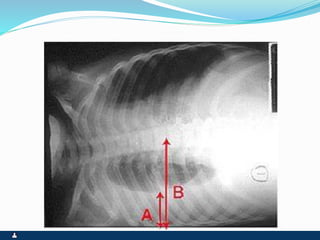

DERRAME PLEURAL

SINTOMAS SINAIS

 DEPENDENTES DA

ETIOLOGIA

 DOR PLEURÍTICA

 TOSSE SECA

 DISPÉIA

 TAQUIPNÉIA

 ABAULAMENTO HOMOLATRAL

DO TÓRAX E ESPAÇOS

INTERCOSTAIS

 DESVIO CONTRALATERAL DO

MEDIASTINO

 EXPANSIBILIDADE REDUZIDA

 FTV ABOLIDO

 MACICEZ

 MV ABOLIDO

 ESTERTORES BRÔNQUICOS E

ALVEOLARES NAS ÁREAS DE

TRANSIÇÃO

 COLUNA MACIÇA EM T11 – SINAL

DE SIGNORELLI